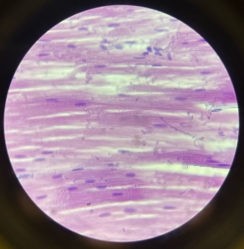

Skeletal Muscle

Skeletal Muscle